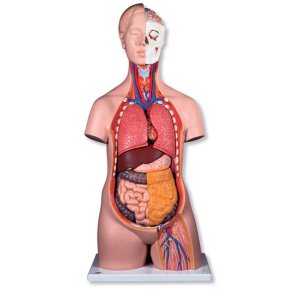

Vare nr. AM11 (C15). Hjerne i 2 dele.

Skåret i mediansnit, og kan således deles i de 2 hjernehalvdele. Står løst på sokkel. En kvalitets model fra verdens førende producent af anatomiske modeller.

Skåret i mediansnit, og kan således deles i de 2 hjernehalvdele. Står løst på sokkel. En kvalitets model fra verdens førende producent af anatomiske modeller.